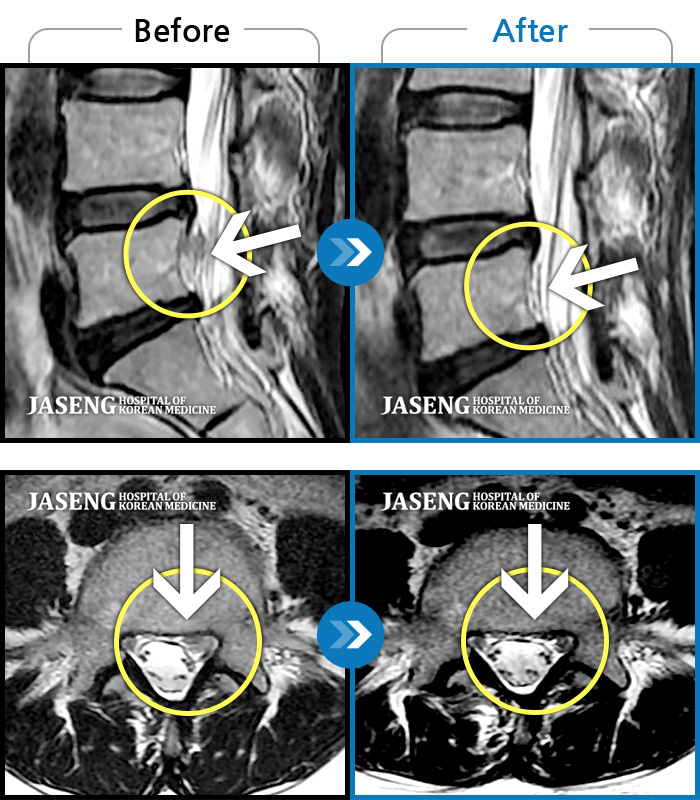

[뱸] 19.11.28~25.05.06

ȯںп Ǹ ǿ ԿǾ, ο ġ ۿ Ƿ ġḦ Ͻñ ٶϴ.